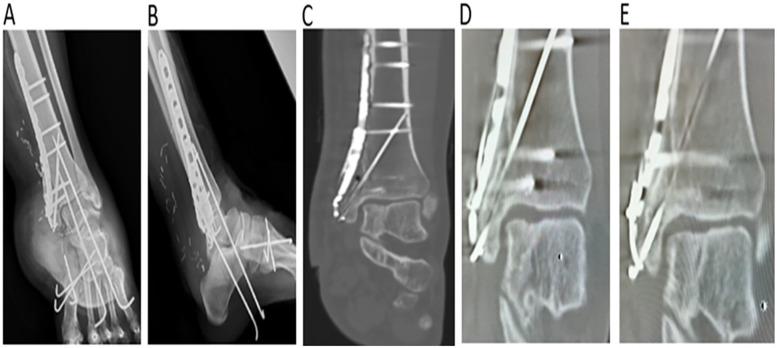

Open fracture-dislocations with significant malleolar bone and soft tissue loss, along with ligament injuries, are complex and often require extensive treatment and staged surgeries. The aim of this report is to highlight treatment strategies and key considerations, including surgical reconstruction with allografts or autografts and various flap techniques as viable options. Additionally, deltoid ligament repair or reconstruction is crucial for surgical success. We report the case of a 29-year-old woman with no significant medical history who sustained an open fracture-dislocation of the left medial malleolus and midfoot due to a lifeboat propeller injury while white water rafting. The injury led to substantial bone and soft tissue loss and deltoid ligament injury. Following multiple wound debridements, the ankle was successfully reconstructed using an AO distal tibia plate, autogenous iliac bone graft, tension band wire, cancellous screw, and free anterolateral thigh flap, with direct deltoid ligament repair. The patient was followed up for 5 years, with favorable outcomes.

伴有明显内踝骨质和软组织缺损以及韧带损伤的开放性骨折脱位较为复杂,通常需要进行广泛治疗和分期手术。本报告旨在强调治疗策略和关键注意事项,包括使用同种异体移植物或自体移植物进行手术重建以及各种皮瓣技术作为可行选择。此外,三角韧带修复或重建对于手术成功至关重要。我们报告了一例29岁女性病例,她既往无重大病史,在白水漂流时因救生艇螺旋桨受伤导致左内踝和中足开放性骨折脱位。该损伤导致大量骨质和软组织缺损以及三角韧带损伤。经过多次伤口清创后,使用AO远端胫骨钢板、自体髂骨移植、张力带钢丝、松质骨螺钉和游离股前外侧皮瓣成功重建了踝关节,并直接修复了三角韧带。对患者进行了5年随访,结果良好。